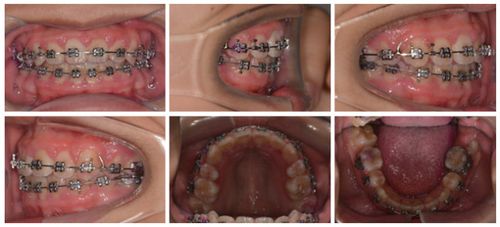

(图片来源网络,侵删)- 口腔卫生维护困难: 固定矫治器(托槽、弓丝)会显著增加清洁牙齿和牙龈的难度,如果患者本身就有牙龈炎,佩戴矫治器后,食物残渣和菌斑更容易堆积,显著加重牙龈炎症,形成恶性循环。